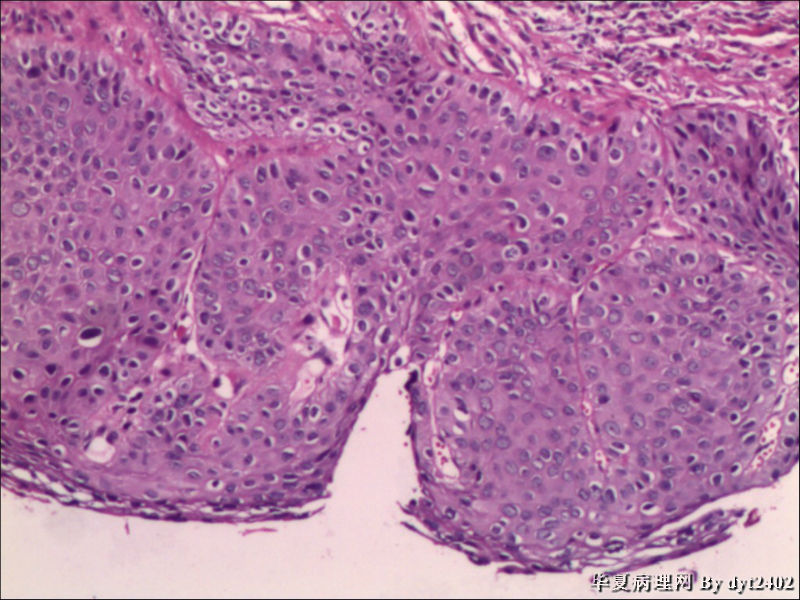

这样的外阴病变 发个原位癌是否合适?

• 这样的外阴病变 发个原位癌是否合适?图3

图3

原位癌够了,不排除其他地方有浸润。

VIN III,做个银染或者标个免疫组化看一下基底膜是否完整。

VIN III